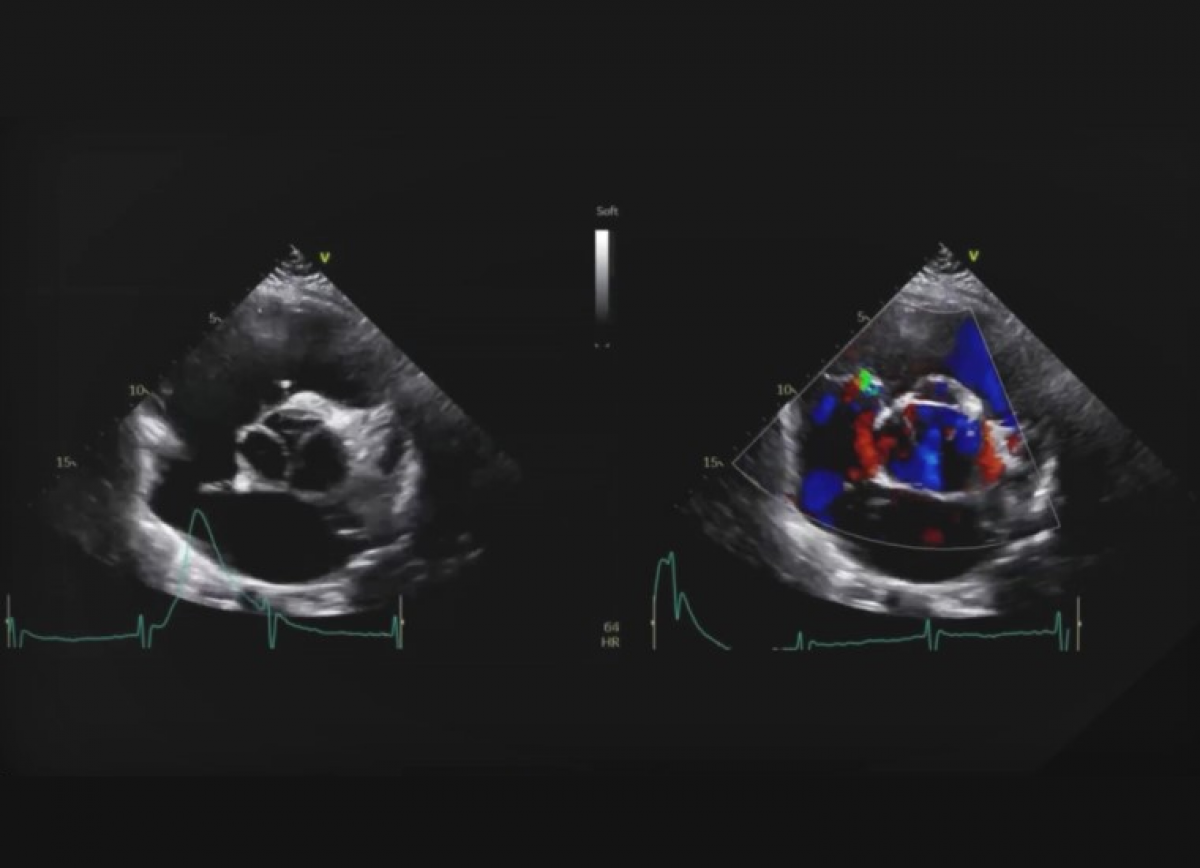

Pacjentka z niewydolnością serca NYHA III i szmerem rozkurczowym

Zespół Marfana. Niedomykalność aortalna z istotnym poszerzeniem opuszki aorty.

Echokardiografia przezklatkowa

Ocena niedomykalności aortalnej.

Ocena aorty piersiowej.

Ocena pacjentów z zespołem Marfana,